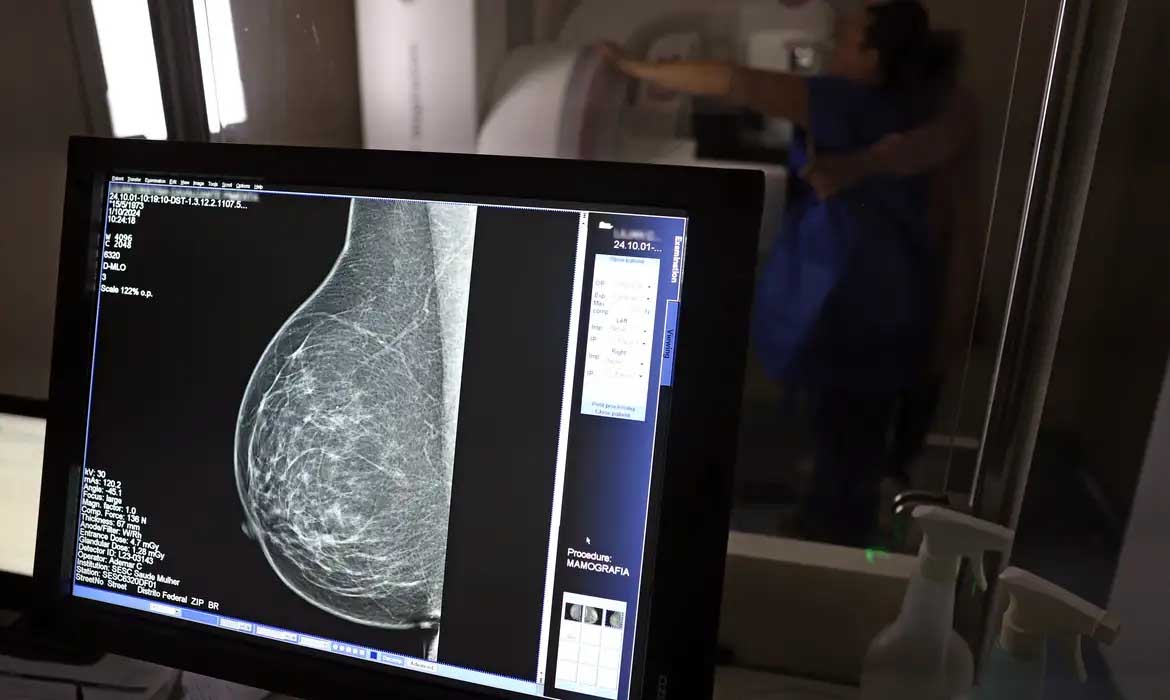

O Ministério da Saúde passou a recomendar o acesso a mamografia, via Sistema Único de Saúde (SUS), para mulheres de 40 a 49 anos – mesmo que não haja sinais ou sintomas de câncer de mama. De acordo com a pasta, a faixa etária concentra 23% dos casos da doença, e a detecção precoce aumenta as chances de cura.

Até então, a orientação era que o exame fosse feito a partir dos 50 anos.

A medida faz parte de um conjunto de ações anunciadas nesta terça-feira (23) voltado para a melhoria do diagnóstico e da assistência. A recomendação para mulheres a partir dos 40 anos é que o exame seja feito sob demanda, em decisão conjunta com o profissional de saúde.

As mamografias via SUS em pacientes com menos de 50 anos, de acordo com a pasta, representam 30% do total, o equivalente a mais de 1 milhão apenas no ano de 2024.

Outra medida anunciada é a ampliação da faixa etária para o rastreamento ativo – quando a mamografia é solicitada de forma preventiva a cada dois anos. A idade limite, até então, era 69 anos. Agora, passa a ser 74 anos. Dados do ministério revelam que quase 60% dos casos de câncer de mama estão concentrados entre 50 e 74 anos.

“A ampliação do acesso à mamografia aproxima o Brasil de práticas internacionais, como as adotadas na Austrália, e reforça o compromisso em garantir diagnóstico precoce e cuidado integral às mulheres brasileiras. O câncer de mama é o mais comum e o que mais mata mulheres, com 37 mil casos por ano”, reforçou a pasta.

Os números mostram que, em 2024, cerca de 4 milhões de mamografias para rastreamento e 376,7 mil exames diagnósticos foram realizados no SUS.